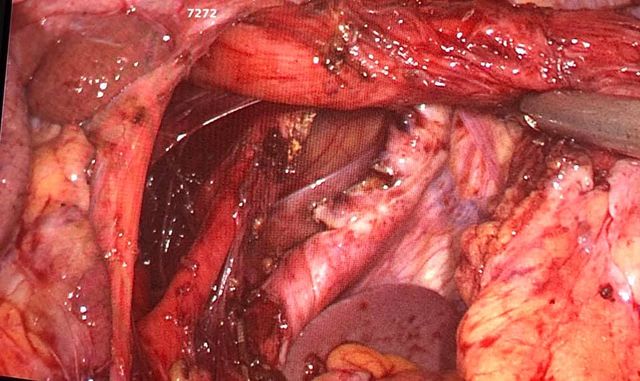

Total pancreaticoduodenectomy with splenectomy done for a 45 yr female with main duct

Total pancreaticoduodenectomy with splenectomy done for a 45 yr female with main duct IPMN with invasive mid-body cancer with bilateral polycystic kidneys. Her EUS, ERCP and fluid cytology , fluid CEA, serum CA19 -9 were all suggestive and a PET showed high uptake in her solid .She is doing well post op but planned for adjuvant CT Rt as had breached capsule and encased splenic vein. Total pancreaticoduodenectomy was frowned upon as a high morbidity surgery due to severe exocrine and endocrine insufficiency with brittle diabetes and ulcerogenicity due to complete loss of pancreatic bicarbonate secretion. But in recent years with easy availability of enzyme supplements, CGM (continuos glucose monitoring devices), insulin pens and long acting PPI the long term QoL of these patients is comparable with partial pancreatectomy patients